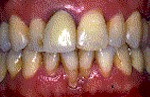

c) Tratamiento para la enfermedad de las encías

En las etapas iniciales de la enfermedad de las encías, el tratamiento consiste en remover la placa y cálculos de las bolsas alrededor de los dientes puliendo y alisando las raíces. Así se eliminan las bacterias y los irritantes que causan la inflamación.

Normalmente el tratamiento permite que la encía se adhiera de nuevo al diente o se contraiga lo suficiente para eliminar la bolsa. En la mayoría de los casos de la enfermedad periodontal inicial requiere un raspado, alisado radicular y una buena higiene oral para obtener resultados satisfactorios.